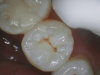

Fig 2. Based on x-ray, clinician was uncertain if caries was present in red circled area.

Figure 2

Figure 1 shows a pretreatment photograph of a tooth No. 20. In Figure 2, the circled area of the x-ray indicates the interproximal area where the clinician was uncertain if caries was present. Though x-rays are useful, transillumination is more sensitive and optimal for detecting caries in the early stages.12 With new devices, clinicians can acquire more information before working on the tooth. As shown in Figure 3, caries was confirmed using the transillumination system (CariVu), though it did not show up on an x-ray. The clinician was able to show the image to the patient. The open-tooth camera image then revealed the extent of the caries in the exact position that was displayed in the transillumination image (Figure 4). This is a significant advantage in minimizing preparations and saving valuable tooth structure.